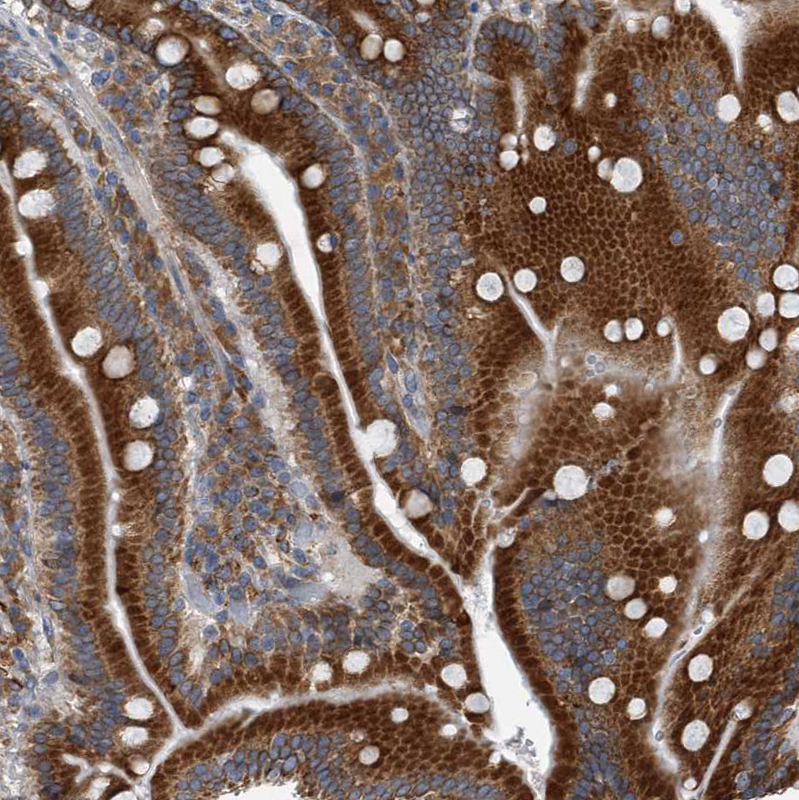

Immunohistochemical staining of human Duodenum shows strong granular cytoplasmic positivity in glandular cells.